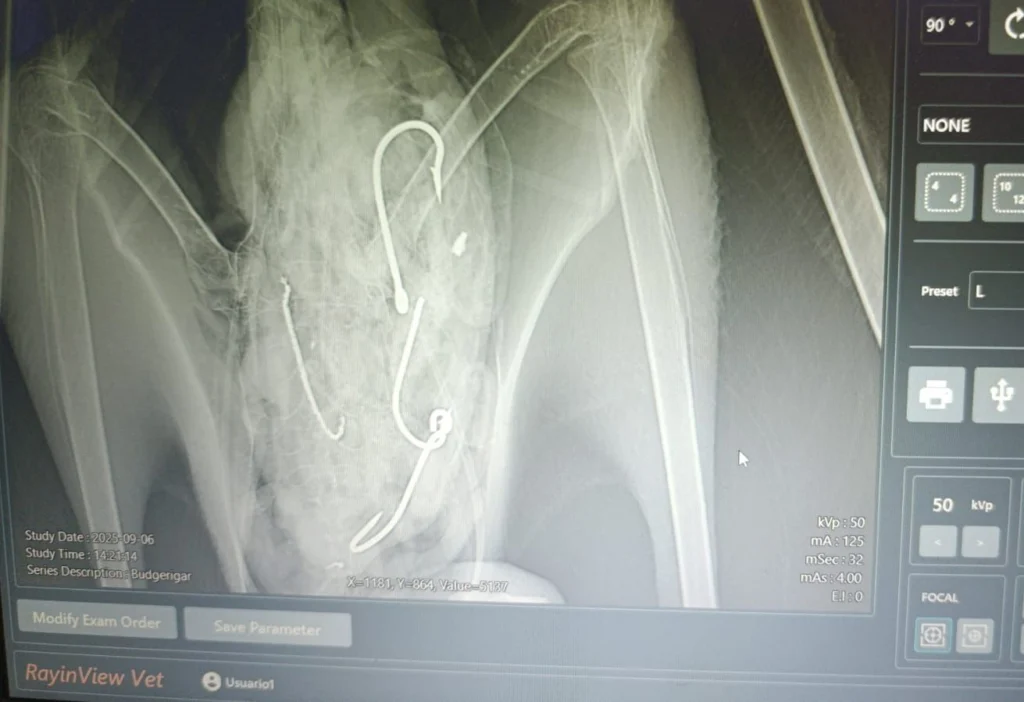

“Through coordination with Ecuador's Ministry of the Environment's local representative (REMACOPSE) and a specialized veterinarian, we successfully removed four fishing hooks from the bird, including one that caused injuries to its esophagus. The type and size of the hooks suggest they came from the artisanal mahi-mahi fishery, which poses a risk to albatrosses. While reducing bycatch in this type of fishery is challenging, we continue to promote best practices and more sustainable tools to minimize incidental seabird capture,” Espín said.